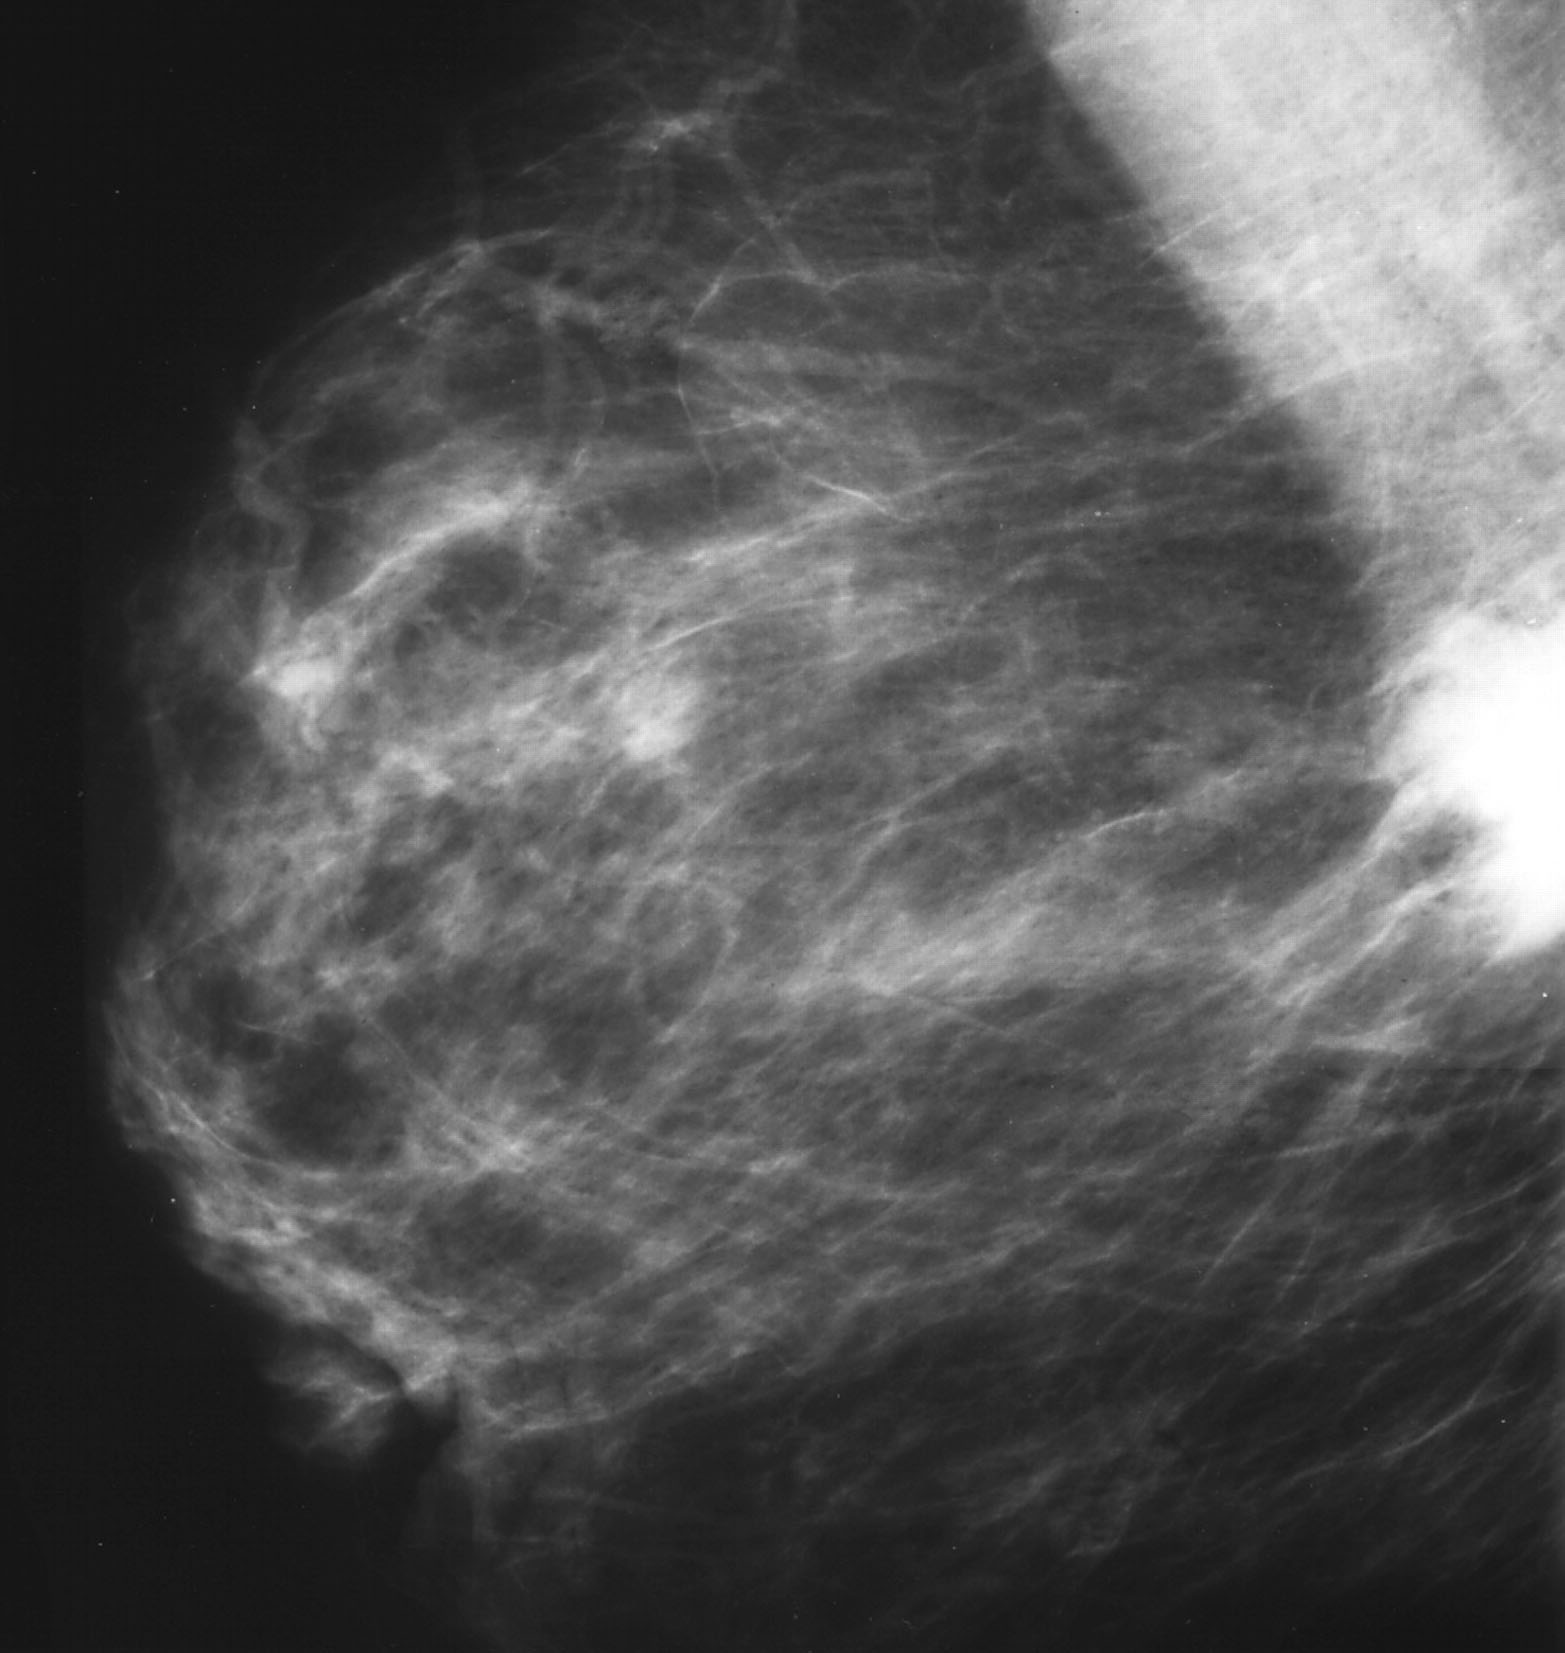

Опухоль на снимке маммографии

Злокачественные опухоли молочных желез